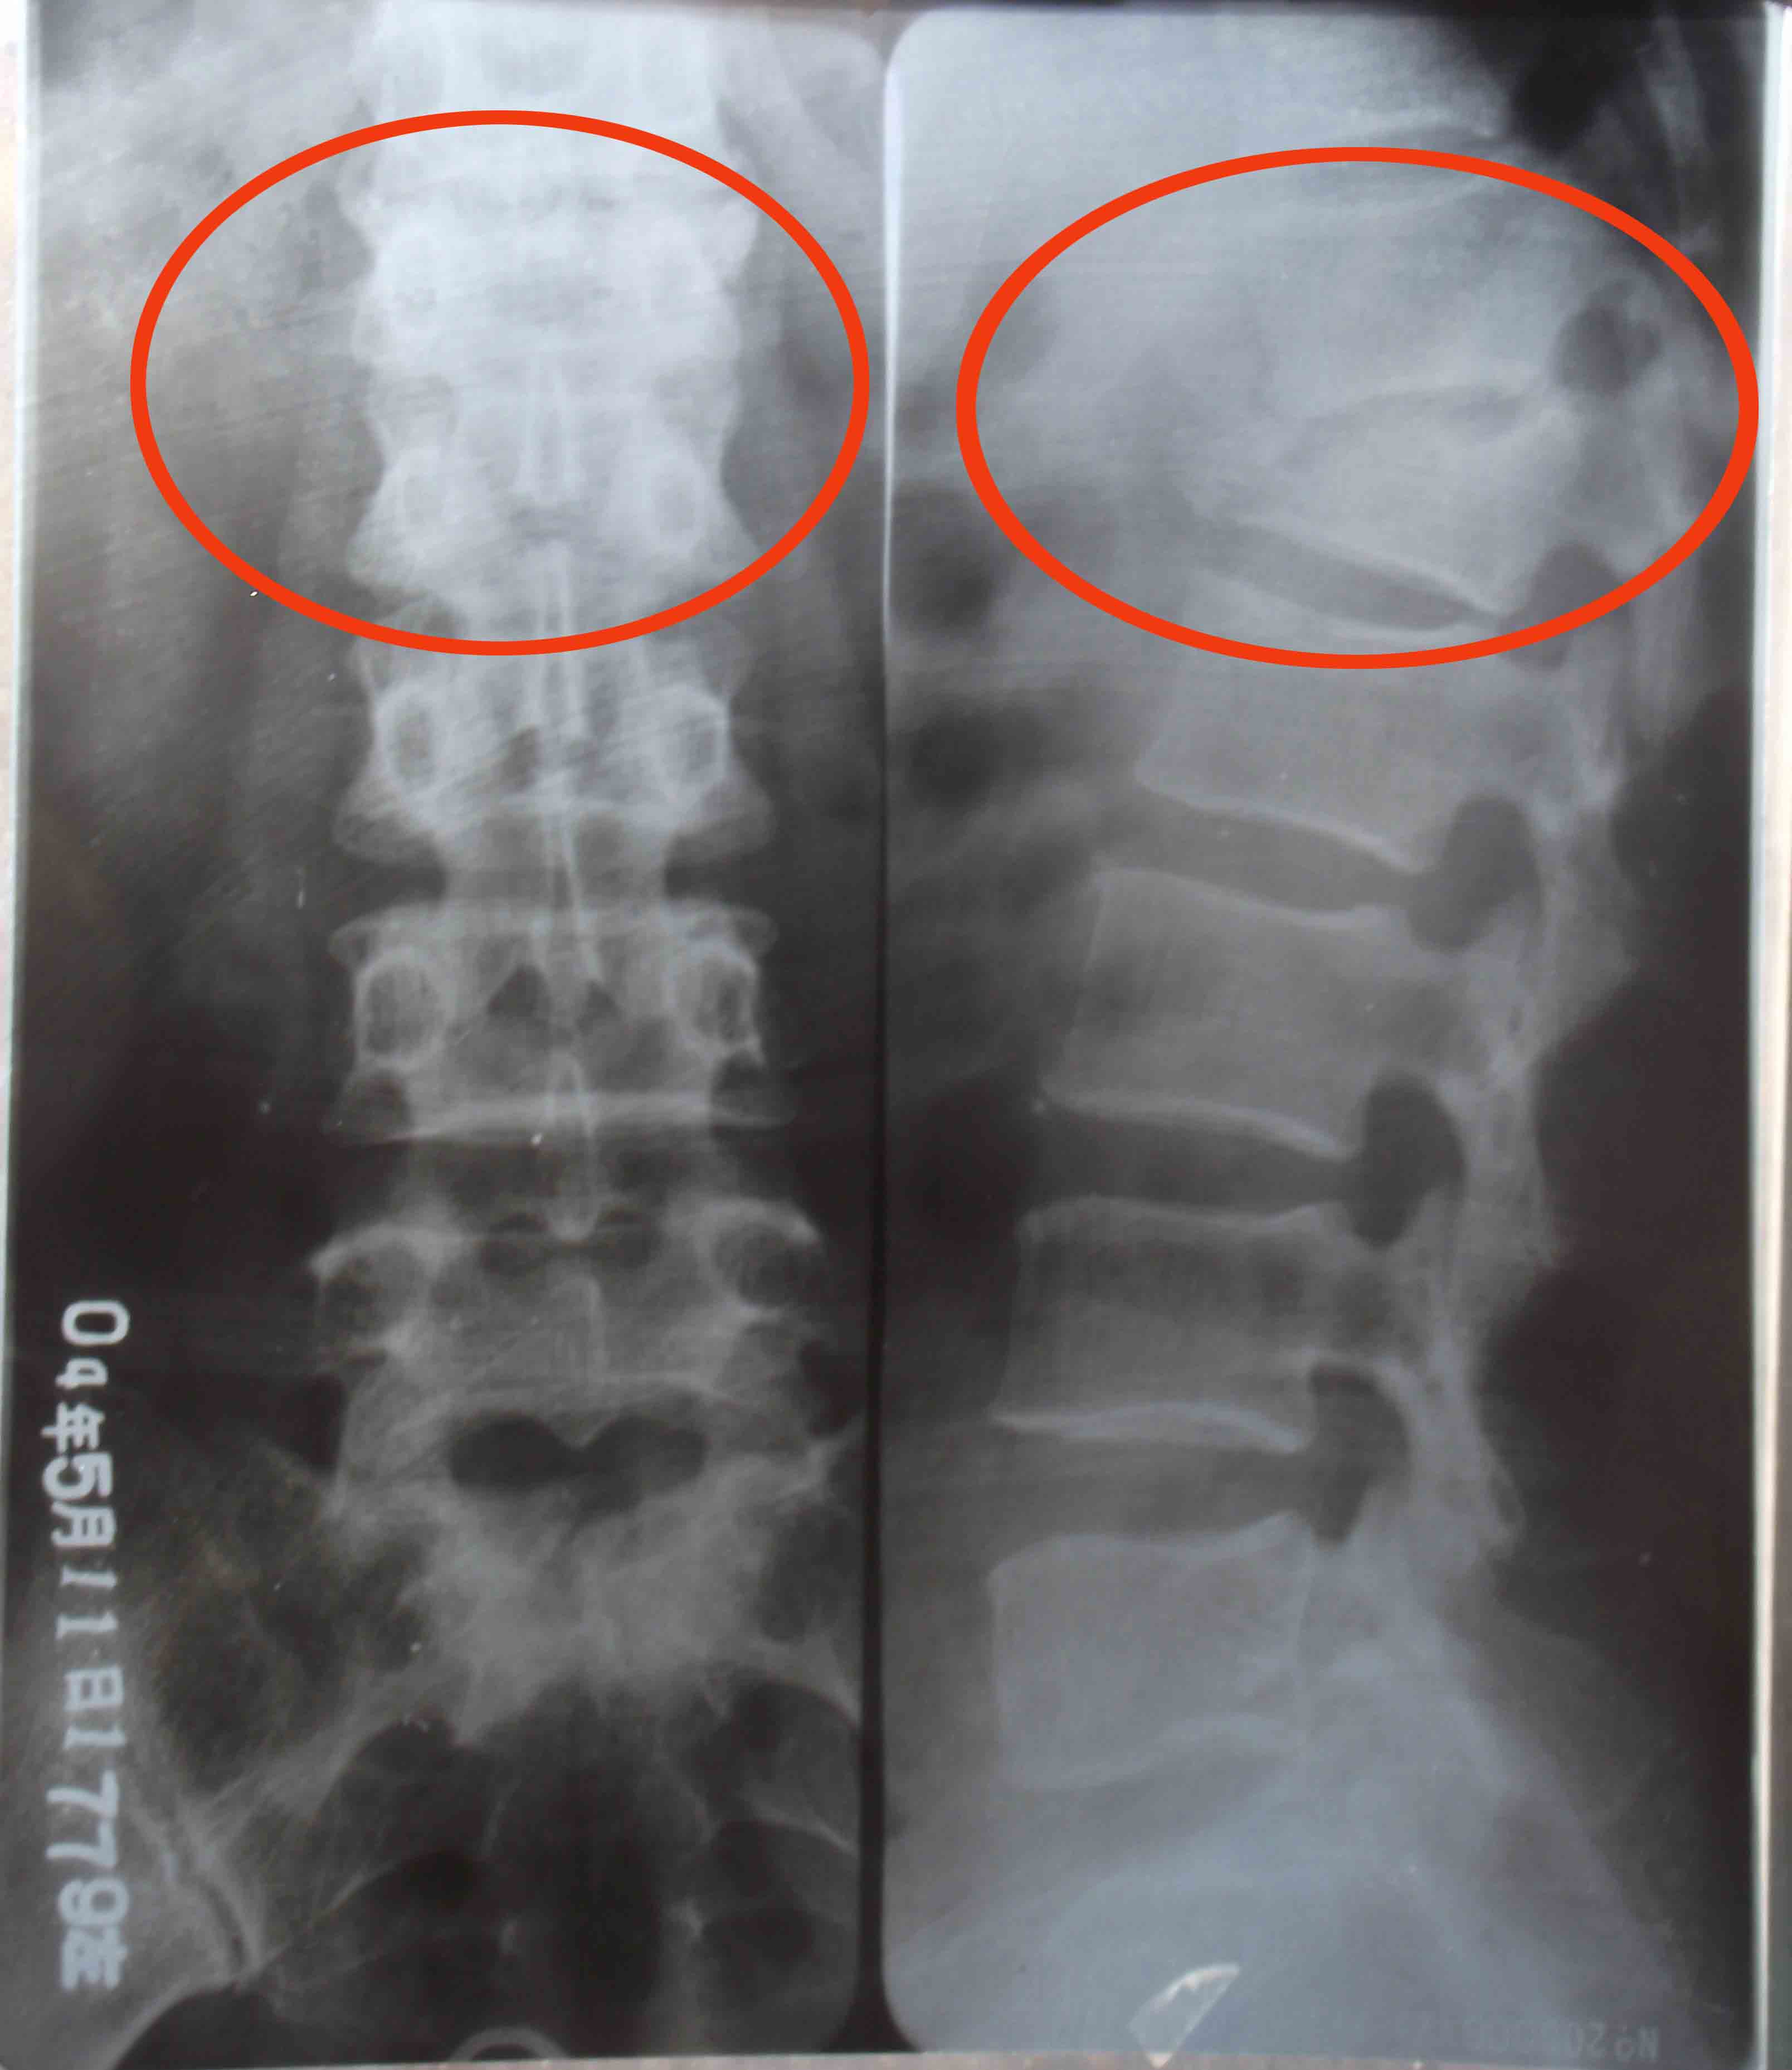

当天半夜我离开家以后,不断更换住处。三月二十九日那天,我刚把房门裂个缝,就见一个贼头贼脑的人正往我这里看,极度的恐惧顿时吓的我不知所措,只想快点离开住处,从窗往外看楼与地面并不高,我就跳了下来,结果受了伤,过路人把我抬到一辆出租车上,当司机知道我的遭遇时他什么都没说,把我送到了一个法轮功学员家。历经一个多月艰难的日子我终于能行走了,那段日子没有医疗(不敢住院怕被绑架),没有家人,只有痛苦和恐惧,若不是有大法的法理、同修的照顾真的很难走过来。后来到医院确诊我的右胳膊肘到手的那段骨头从胳膊肘里撞出来了,胸椎十二节和腰椎一节压缩性骨折,后来成为两椎体融合成一个椎体,当医生看到X光片子惊讶的说:“这是要瘫痪的!”当时腰椎骨折手术得十万余元,我被单位开除,没有生活来源,没钱医治。也只能在弟、妹的援助下做了胳膊的手术,术后胳膊再也不能直伸了,腰部连洗衣服都疼,更不能干重活,终生残疾。